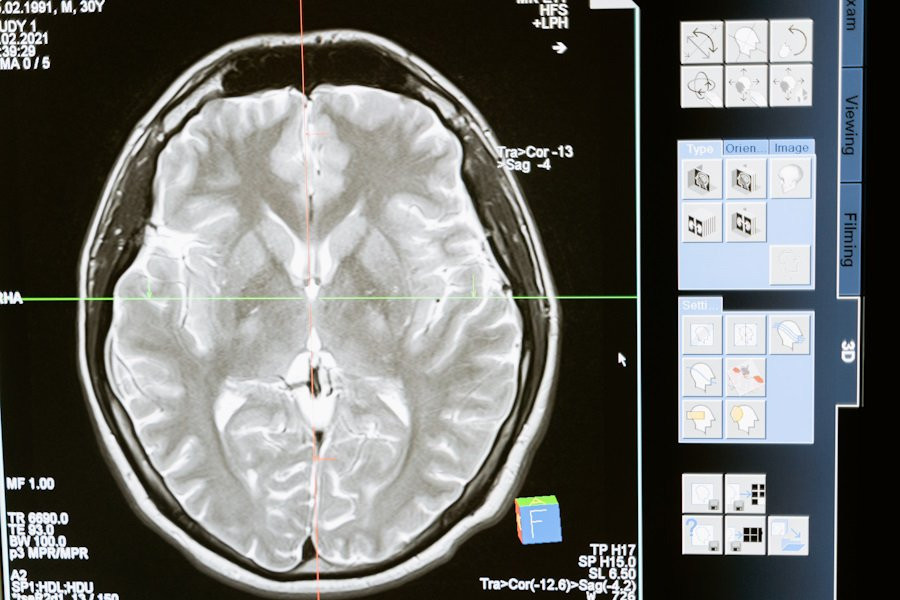

Интернациональная группа учёных, проведя масштабное исследование, выявила пять моделей старения мозга у человека. В своей публикации на портале Nature Medicine, ученые проанализировали тысячи сканов МРТ с помощью машинного обучения, чтобы понять, как старение влияет на мозг.

Процесс старения мозга зависит от множества факторов, включая образ жизни, генетику и различные заболевания, связанные с возрастом. Магнитно-резонансная томография (МРТ) и искусственный интеллект помогли исследователям выявить нейроанатомические изменения, происходящие с возрастом. Проще говоря, ИИ помог ученым понять, какие именно части мозга страдают больше всего и как это связано с рисками для здоровья.

Ученые использовали инновационный метод глубокого обучения, Surreal-GAN, чтобы изучить данные 49 482 человек из 11 различных исследований. Они выявили пять доминирующих моделей атрофии мозга, которые были количественно оценены для каждого участника с помощью специальных показателей, названных R-индексами. Эти индексы показывают, как различные биомедицинские, жизненные и генетические факторы влияют на изменения в мозге.